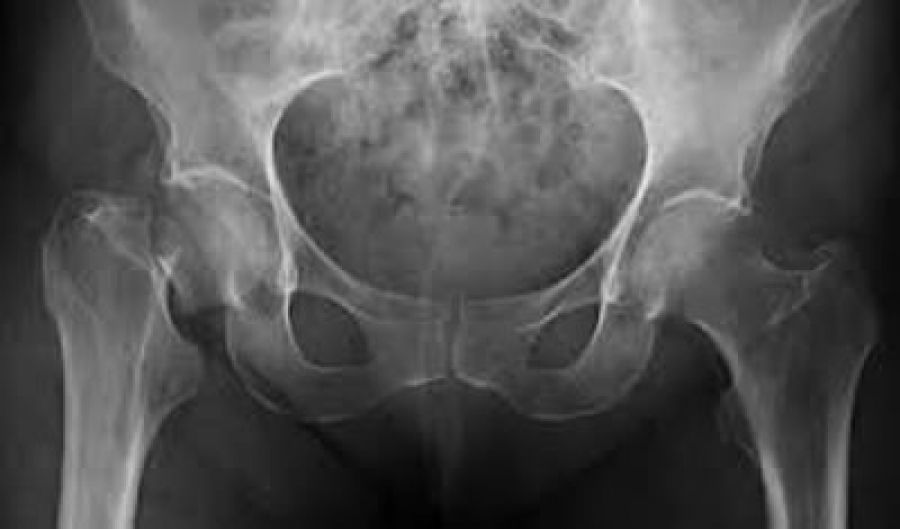

Según cifras del Instituto Mexicano del Seguro Social, 10 millones de mexicanos sufren osteoporosis, lo que significa un aumento de fracturas. De las personas que padecen la enfermedad, el 18% son mujeres de entre 35 y 65 años. Además, afirman datos oficiales, entre las mujeres mayores de 50 años el riesgo de muerte por fractura de cadera es tan grave como el de muerte por cáncer, y 8% de mujeres y 5% de hombres tienen probabilidades de sufrir una fractura de cadera después de esa edad.

Otro dato importante es que entre las mujeres el riesgo de fracturas es de 2 a 3 veces mayor que en los hombres, por lo que 75% de esas lesiones por osteoporosis las padecen ellas. Al respecto, en su blog la empresa de lácteos Lyncott, basada en especialistas, recomienda para las mujeres entre los 19 y 49 años un aporte diario de 1000 mg de calcio acompañado de 400 a 1000 UI, mientras que para las mayores de esa edad dosis de 1200 mg y de 800 a 2 mil UI, respectivamente.